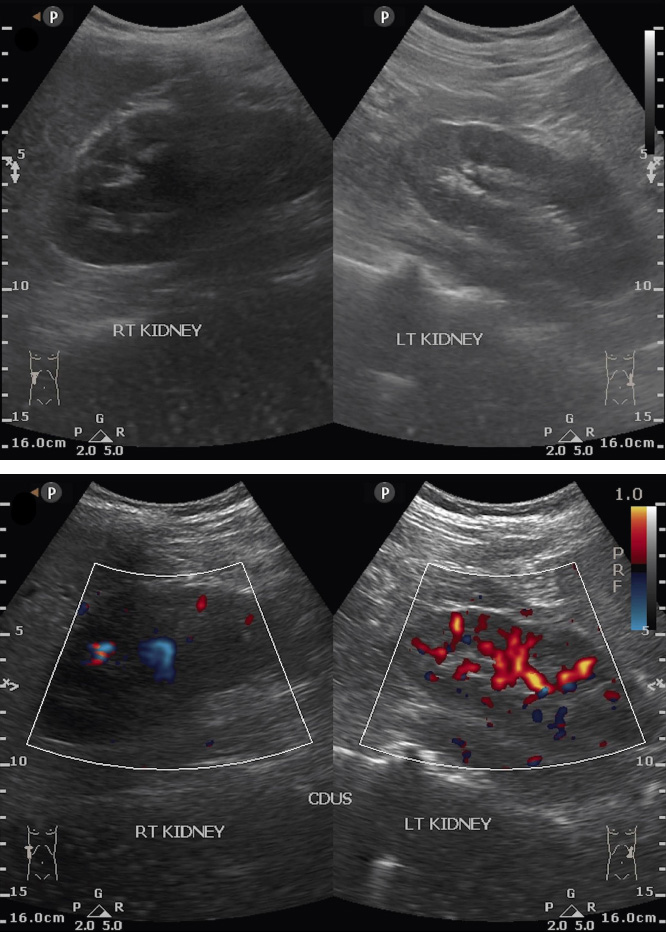

The Doppler ultrasound showed decreased vascularization in the right kidney with mild hydronephrosis (Fig. 1). Based on the symptoms, the team suspected a renal arteriovenous fistula and proceeded with renal embolization without prior CT angiography.

Pre-embolization ultrasound showing a decrease in vascularization in the right kidney with moderate hydronephrosis.